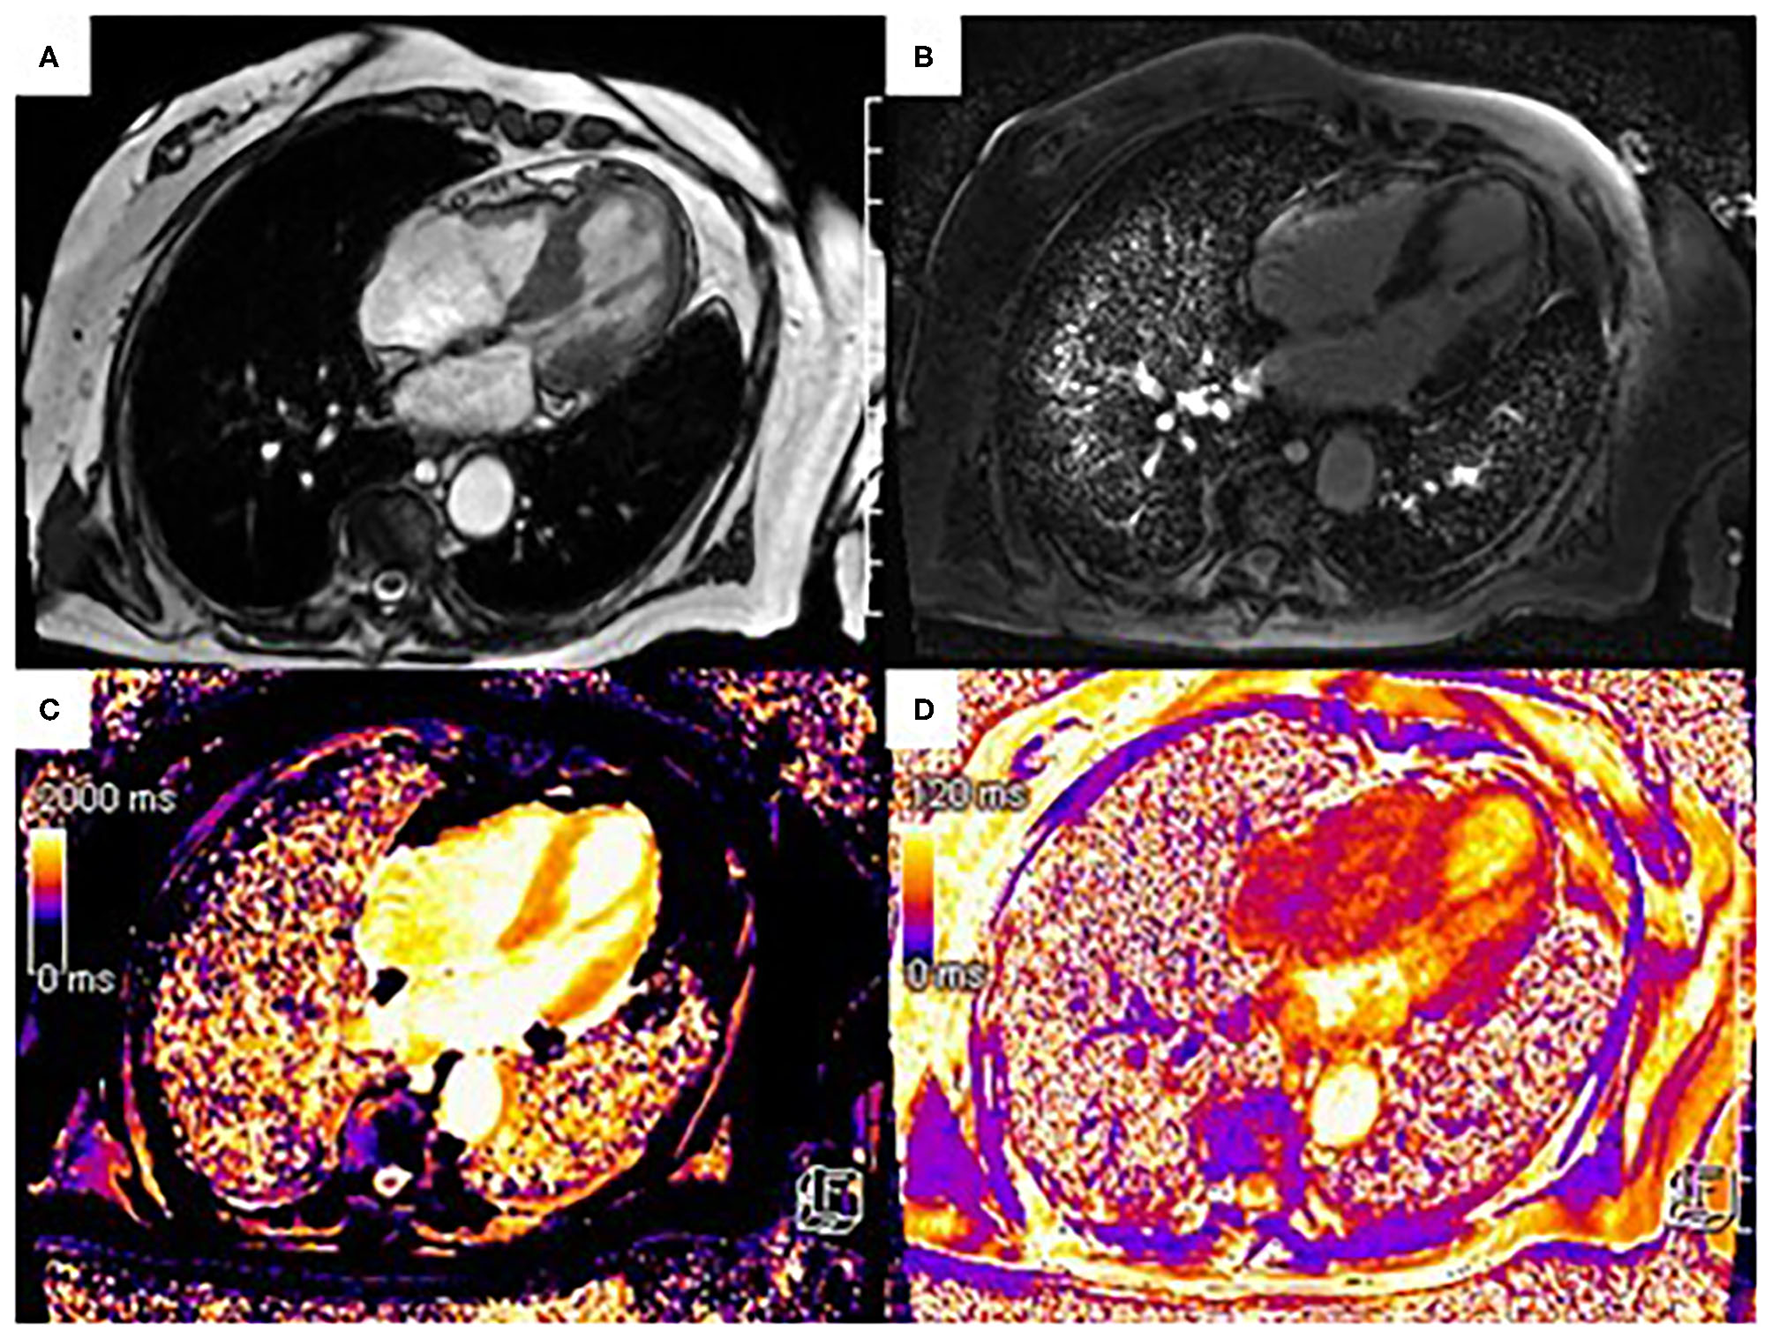

The CMR patterns observed in myocarditis typically include intra-myocardial or subepicardial LGE, distinct from the subendocardial or transmural enhancement seen in ischemic etiologies. In the acute setting, extensive myocardial oedema can be accompanied by a transitory increased in wall thickness (Figure 2).

Figure 2

33-year-old presented with troponin positive chest pain and inferior ST elevation on ECG. He reported recent flu-like symptoms following mRNA COVID-19 vaccination. (A) is the post-contrast steady state free precession (SSFP) cine showing a bright signal intensity in keeping with myocardial oedema due to acute myocardial injury, which is also in keeping with the T2-STIR imaging (B) and T2 mapping (D) images which demonstrate high signal intensity in the mid lateral wall correlating with subepicardial late enhancement on gadolinium imaging (C). The pattern of myocardial injury noted is in keeping with acute myocarditis. The areas of abnormalities are indicated by white arrows.